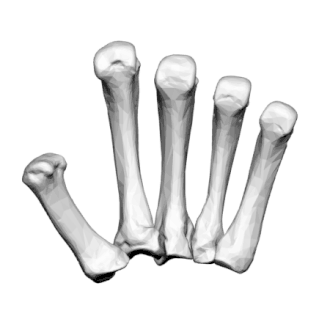

Os métacarpiens, vue médiale

Os métacarpiens, vue antérieure